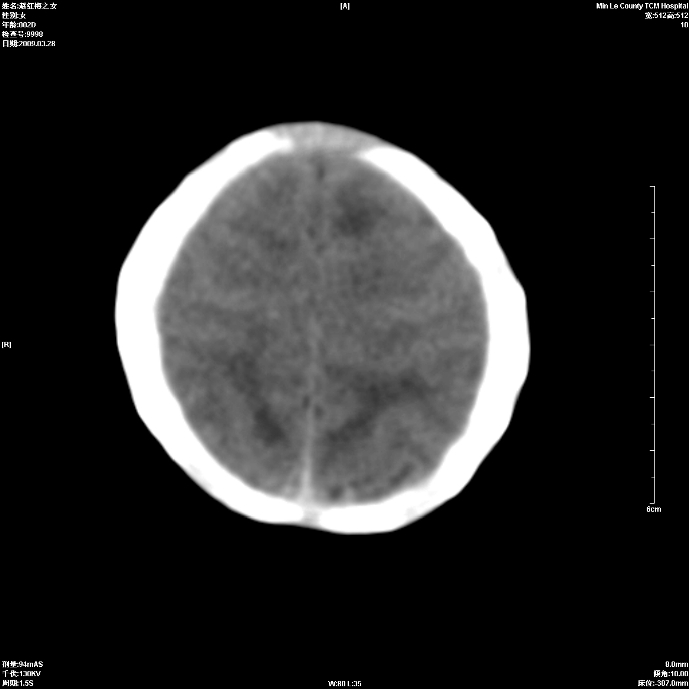

标题: PED1815:患儿出生两天,哭闹不安,囟门饱满 [打印本页]

标题: PED1815:患儿出生两天,哭闹不安,囟门饱满

少量蛛网膜下腔出血,有窒息史吗?

支持考虑新生儿缺血缺氧性脑病伴蛛网膜下腔出血,请结合临床,建议随访复查

缺血缺氧性脑病伴蛛网膜下腔出血.

支持缺血缺氧性脑病伴少量蛛网膜下腔出血。

支持 1)缺氧缺血性脑病。2)蛛网膜下腔出血。

z新生儿缺血缺氧性脑病,蛛网膜下腔出血!

若有窒息史,考虑缺血缺氧性脑病伴少量蛛网膜下腔出血。